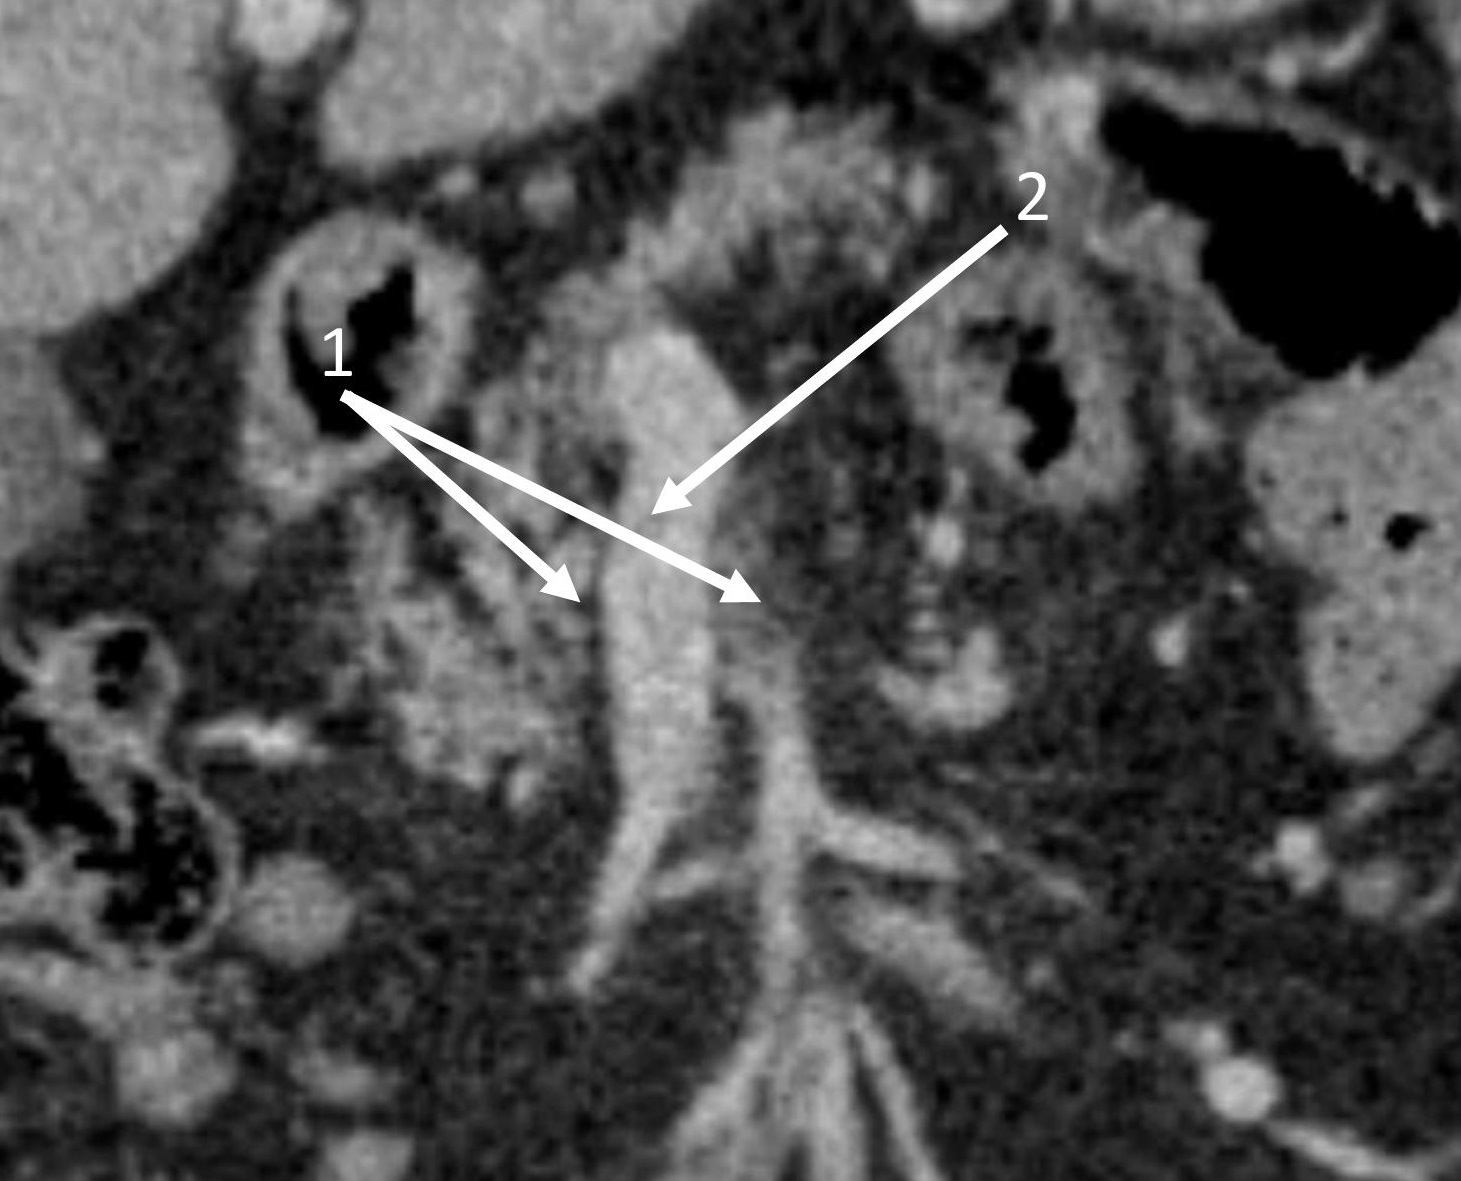

|  | 3. Состояние опухоли до начала неоадъювантной терапии | |

| Тема | ||

| Тип | Исследовательские инструменты | |

|

Посмотреть

(229KB)

| Метаданные ▾ | |